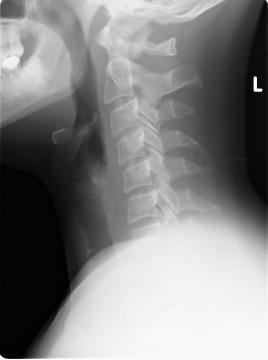

pierre29 - 9.8.2012 7:25:21 Dobrý den,před měsícem jsem prodělal polohové vertigo při obracení v posteli na levý bok, vertigo trvalo cca 1-2 min. a bylo provázeno pocitem na zvracení a trošku zvracením a rozmazaným viděním, druhý den se mi stalo totéž (bez zvracení) při otočení na levý a po chvíli znovu i na pravý bok. Byla mi provedena různá vyšetření na ORL a neurologii (CT, lumbální punkce, EEG, evokované potenciály VEP a BAEP, polohové testy a nic nemylo nalezeno). Ve výsledcích vyšetření mám nystagmus=0, testy na BPPV negativní). Byl jsem propuštěn s tím, že jde o suspektní polohové vertigo a budu několik týdnů užívat lék Betaserc. Na neurologii mi bylo řečeno, že to je vše a že jsem neurologicky i objektivně zdravý. Závrať se již nevrátila, nicméně od té doby se mi několikrát denně stane, že mám při čtení nebo např. koukání na televizi pocit, že mi trošku škubnou/mírně ujedou oči doleva a při tom mnou projede teplo do žaludku (něco jako leknutí) a někdy mi při tom bouchne silně srdce. Nejsem si jist, zda se tak děje najednou nebo je nejdřív pohyb očí a až potom projetí tepla a bouchnutí. Určitě bych měl také uvést, že jsem před třemi roky měl problémy s úzkostmi a beru lék elicea. Od chvíle, co ho užívám jsem ale žádné problémy nepociťoval a normálně funguji. Vím, že neznáte konkrétní případ, ale zajímal by mne spíše Váš názor: 1) může být příčinou pocitů v očích (a případně i vertiga) páteř? (dle rtg mám plně vyhlazenou krční a bederní lordózu a počínající změny na obratlích c2 a c3 viz přiložený rtg), 2) může být příčinou pocitů v očích psychika a stres? (od chvíle hospitalizace jsem neustále ve strachu, že může jít o nádor na mozku, protože příliš nevěřím, že jsem zdraví, když mám ony pocity v očích). Děkuji předem za Váš čas a případnou odpověď.Petr